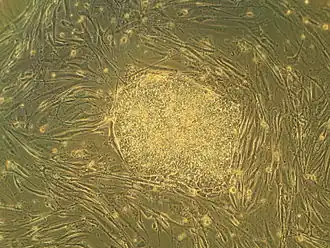

Some of the biomedical approaches within the field of regenerative medicine may involve the use of stem cells.[7] Examples include the injection of stem cells or progenitor cells obtained through directed differentiation (cell therapies); the induction of regeneration by biologically active molecules administered alone or as a secretion by infused cells (immunomodulation therapy); and transplantation of in vitro grown organs and tissues (tissue engineering).[8][9]